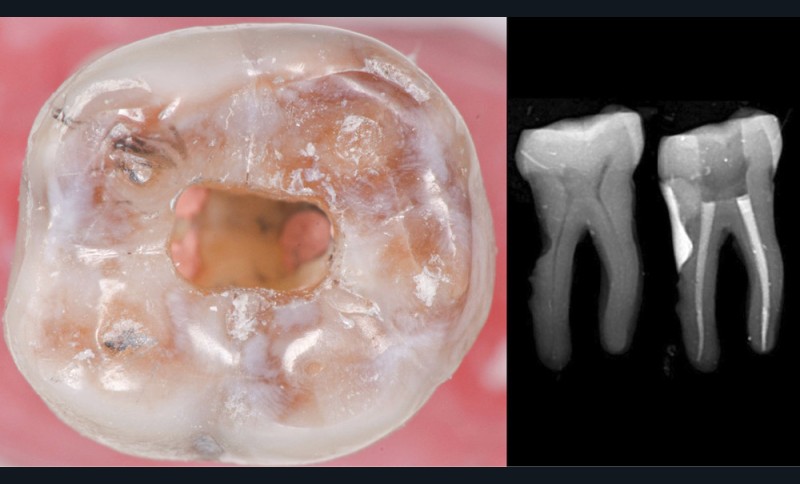

Une cavité d’accès trop large optimiserait le pronostic endodontique mais compromettrait le pronostic biomécanique. C’est le cas de la cavité d’accès traditionnelle, qui a longtemps été « au service » du praticien réalisant le traitement canalaire (dentist-centered dentistry ou dentisterie centrée sur le praticien). Les étapes d’instrumentation, d’irrigation et d’obturation étaient ainsi facilitées grâce à des accès visuel et instrumental exagérés, aux dépens de structures dentaires saines (fig. 4).